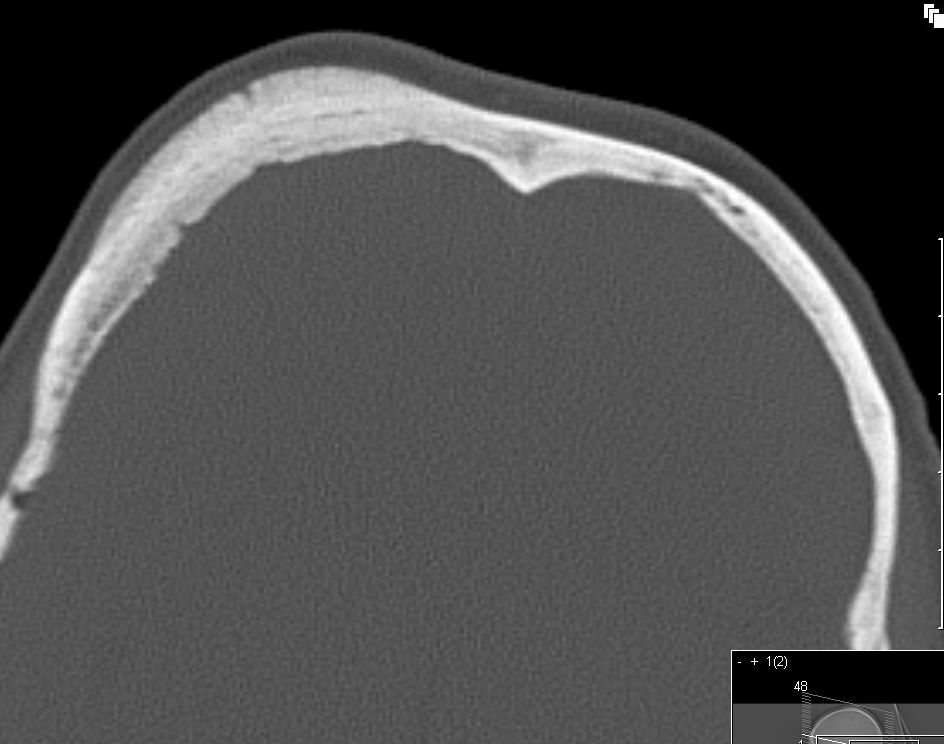

| össäres Meningeom |

53-jährige Frau mit einer Verdickung des Os frontale rechts. Nach CT VD M. Paget. Wegen Größenzunahme Operation. Histologie: ossäres meningotheliales Meningeom WHO-Grad I. | ![]() |